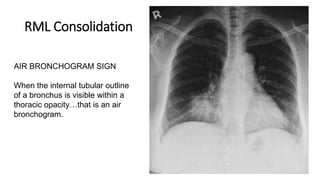

RML Consolidation

AIR BRONCHOGRAM SIGN

When the internal tubular outline

of a bronchus is visible within a

thoracic opacity…that is an air

bronchogram.

Rt border of heart not clear –

(Silhoutte Sign)